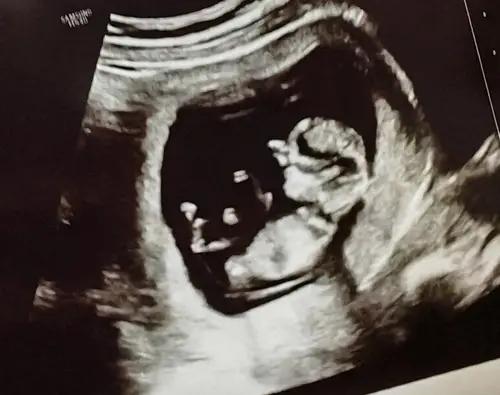

Eerlijk gezegd, kan ik bij alle onderstaande foto’s niets uithalen.. ze zijn te wazig, nub niet goed zichtbaar

Wat denken jullie?

Ik ben een nub-noob dus wil ook graag bij de andere dames checken of ik geen onzin uitkraamt: je ziet de nub hier goed (als het ten minste de nub is en niet een stuk van het linkerbeentje) en op basis van de hoek met de ruggenwervel zou dit een meisje zijn.